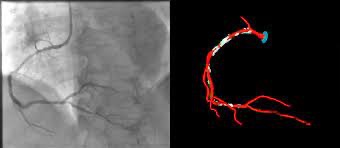

Στεφανιογραφία – Η βάση της επεμβατικής καρδιολογίας

Η στεφανιογραφία είναι η βασική διαγνωστική εξέταση της επεμβατικής καρδιολογίας.

Επιτρέπει την άμεση απεικόνιση των στεφανιαίων αρτηριών και τον εντοπισμό στενώσεων.

Αν βρεθεί σοβαρή στένωση, η θεραπεία μπορεί να γίνει την ίδια στιγμή.